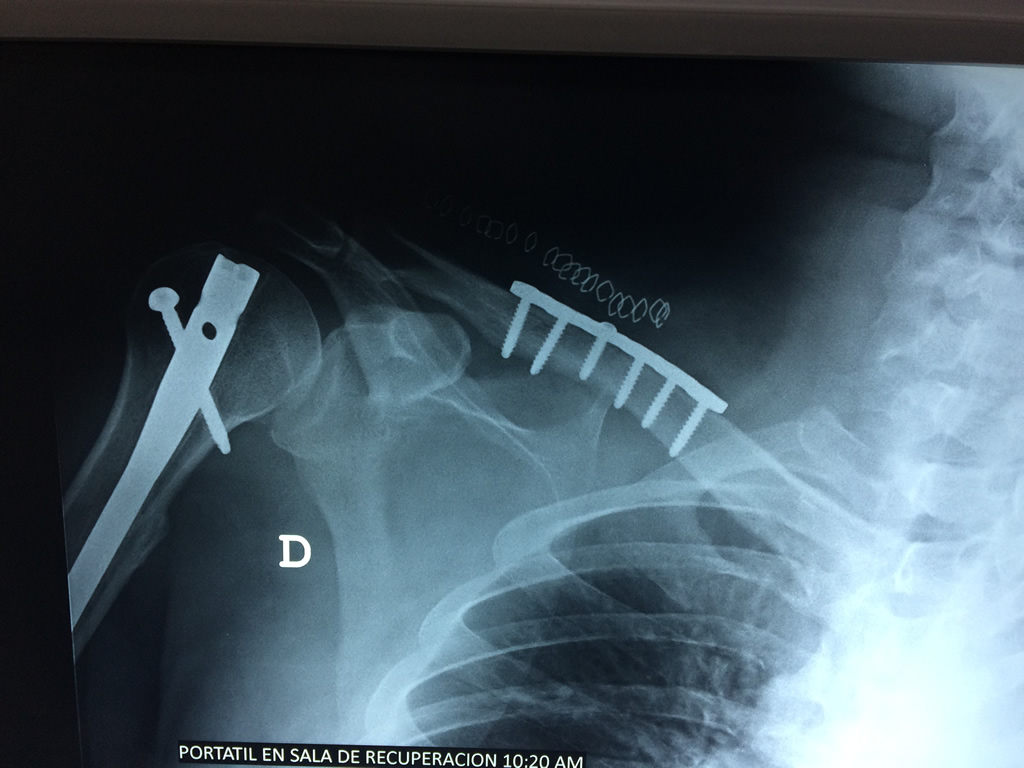

Clavícula

La clavícula es un hueso largo, con forma de "S" itálica, situado en la parte anterosuperior del tórax. Junto con la escápula forman la cintura escapular. Se puede palpar por toda su longitud y se extiende del esternón al acromion de la escápula, siguiendo una dirección oblicua lateral y posterior.

Se considera el único medio de unión entre el miembro superior y el tórax. A pesar de su aspecto, similar al de un hueso largo, posee una estructura semejante a la de un hueso plano, ya que carece de epífisis y de diáfisis, lo que la harían entrar dentro de la clasificación de hueso largo. Carece de un canal medular propiamente dicho.